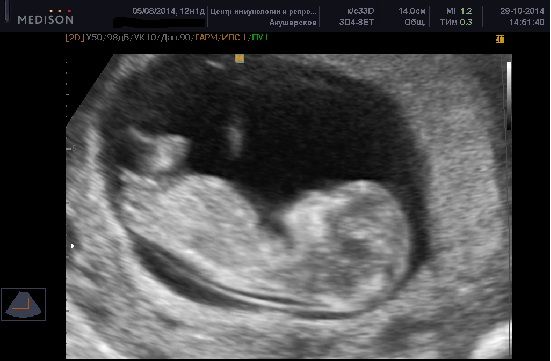

Для определения Пола на ранних сроках нужен такой ракурс, в другом увы никак.На втором триместре можно ещё в другом ракурсе посмотреть:из-под попы, как будто ребёнок сел на камеру.